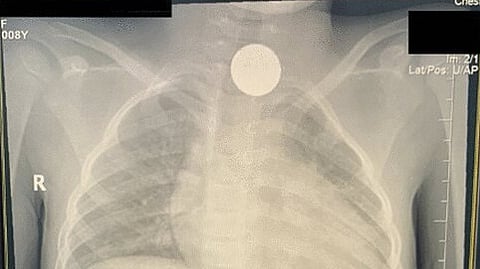

وبحسب المتحدثين فإن الجسم المعدني ظهر في أشعة الصدر التي أُجريت للطفلة قبل أربع سنوات خلال فحص روتيني، واعتقد حينها الطبيب المعالج أنها قد تكون قطعة من قلادة أو أزرار ملابسها، إلا أنه بعد إجراء أشعة صدر جديدة مؤخرًا لوحظ وجود الجسم ذاته، وهو ما كشف عن وجود خطأ، وضرورة التدخل الطبي السريع.